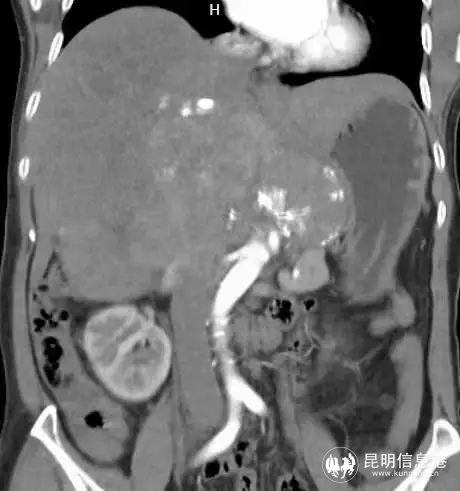

57岁的吴女士,从今年年初开始,感觉体力不断下降,白天易疲劳,提不起精神,胃口也不好,体型日渐消瘦,不久出现右上腹隐约疼痛症状。家人送医后CT检查结果显示:中、上腹巨大不均质肿物,填塞肝门,贴压胆囊、胰腺、右肾、门静脉、下腔静脉,考虑恶性。

图为术前影像

患者入院后,省三院肝胆胰外科专家团队经过仔细检查后发现该患者中上腹巨大不均质肿物已经填塞肝门,与肝实质分界不清,贴压胆囊、胰腺、右肾、门静脉、下腔静脉,手术操作的空间非常小。其次,患者身体基础条件十分不好,长期高血压,心肺功能极差,肝功能下降,手术难度极大。